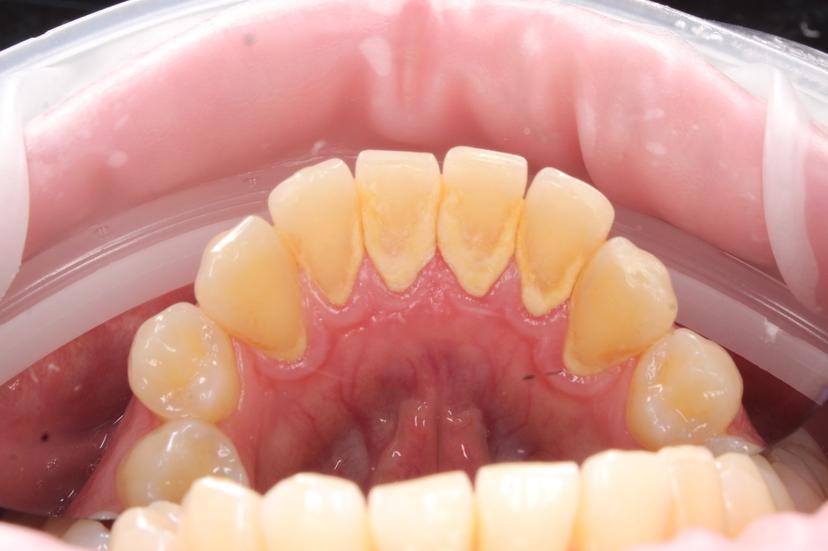

Снятие пигментированного зубного налета системой AirFlow зубов верхней челюсти

Снятие пигментированного зубного налета системой AirFlow на нижней челюсти

Профессиональная гигиена полости рта с использованием системы AirFlow для снятия пигментированного налета, а так же ультразвуковым скейлингом для снятия твердых зубных отложений (зубной камень)